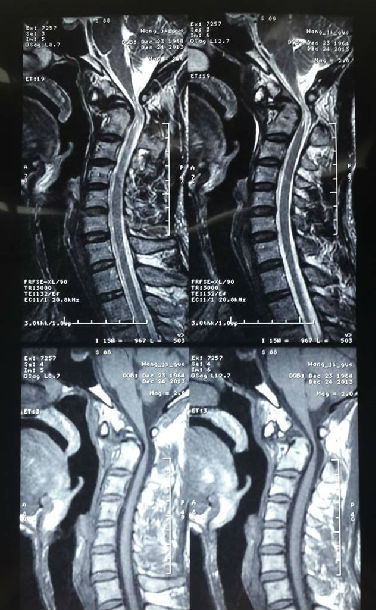

手术前MRI显示:寰枢椎脱位(C1-C2间水平脱位10mm),脊髓明显受压变细。

寰枢椎脱位枕颈融合术前、术后对比,可见寰枢椎脱位复位良好,延颈髓受压明显改善,脊髓空洞缩小。